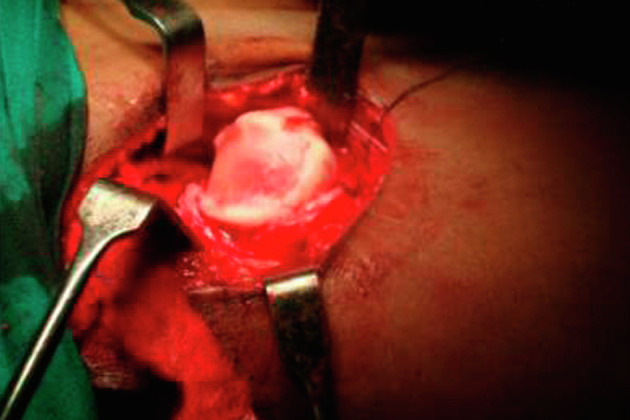

This review brings together a multidisciplinary, multinational team of experts to discuss the current state of knowledge in the detection and treatment of hip displacement in cerebral palsy (CP), a global public health problem with a high disease burden. Though common themes are pervasive, different views are also represented, reflecting the confluence of traditional thinking regarding the aetiology and treatment of hip displacement in CP with emerging research that challenges these tried-and-true principles. The development of hip displacement is most closely related to gross motor function, with radiographic surveillance programs based on the Gross Motor Function Classification System (GMFCS), the goal being early detection and timely treatment. These treatments may include non-operative methods such as abduction bracing and Botulinum Neurotoxin A (BoNT-A), but outcomes research in this area has been variable in quality. This has contributed to conflicting opinions and limited consensus. Soft tissue lengthening of the hip adductors and flexors has traditionally been employed for younger patients, but population-based studies have shown decreased survivorship for this treatment when performed in isolation. Concerns with the identification of hip displacement in very young children are raised, noting that early reconstructive surgery has a high recurrence rate. This has prompted consideration of viable minimally invasive alternatives that may have better success rates in very young children with CP, or may at least delay the need for osteotomies. Recent reports have implicated the role of abnormal proximal femoral growth and secondary acetabular dysplasia as a primary cause of hip displacement, related to ambulatory status and abductor function. As such, guided growth of the proximal femur has emerged as a possible treatment that addresses this purported aetiology, with promising early results.

本综述汇集了一支多学科、多国专家团队,共同探讨了脑性瘫痪(CP)髋关节移位的检测和治疗知识现状,脑性瘫痪是一个疾病负担沉重的全球性公共卫生问题。虽然普遍存在共同的主题,但也有不同的观点,这反映了有关脑瘫髋关节移位的病因和治疗的传统思想与挑战这些屡试不爽的原则的新兴研究的交汇。髋关节移位的发生与粗大运动功能的关系最为密切,根据粗大运动功能分类系统(GMFCS)制定的影像学监测计划,其目标是早期发现和及时治疗。这些治疗可能包括非手术方法,如外展支撑和肉毒杆菌神经毒素 A(BoNT-A),但该领域的成果研究质量参差不齐。这导致了意见分歧和共识有限。髋关节内收肌和屈肌的软组织延长术传统上用于年轻患者,但基于人群的研究显示,如果单独进行这种治疗,存活率会降低。研究还提出了对年幼儿童髋关节移位的识别问题,并指出早期重建手术的复发率很高。这促使人们开始考虑可行的微创替代方法,这些方法可能对年幼的 CP 儿童有更好的成功率,或至少可以推迟截骨手术的需要。最近的报告显示,股骨近端发育异常和继发性髋臼发育不良是导致髋关节移位的主要原因,与活动能力和外展功能有关。因此,引导股骨近端生长已成为解决这一所谓病因的可能治疗方法,并取得了令人鼓舞的早期效果。